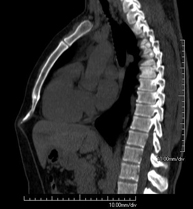

- Tórax- TC Tórax Prueba diagnóstica que consiste en obtener imágenes del tórax de alta definición anatómica (pulmones, corazón, mediastino, grandes vasos, caja torácica, etc.) mediante el empleo de un equipo de TC (Tomografía Computarizada). Dichas imágenes se estudian posteriormente en una estación de trabajo que permite reconstrucciones bidimendionales en diferentes planos del espacio y también reconstrucciones 3D (volumétricas). Algunos estudios requieren el empleo de contraste yodado para mejorar la definición de las imágenes. Prueba diagnóstica que consiste en obtener imágenes del tórax de alta definición anatómica (pulmones, corazón, mediastino, grandes vasos, caja torácica, etc.) mediante el empleo de un equipo de TC (Tomografía Computarizada). Dichas imágenes se estudian posteriormente en una estación de trabajo que permite reconstrucciones bidimendionales en diferentes planos del espacio y también reconstrucciones 3D (volumétricas). Algunos estudios requieren el empleo de contraste yodado para mejorar la definición de las imágenes.

- Angio-TC Aorta torácica Prueba diagnóstica que consiste en el estudio de la aorta torácica (principal arteria del tórax) mediante el empleo de un equipo de TC (Tomografía Computarizada). Esta técnica requiere el empleo de contraste yodado, y proporciona imágenes de alta definición anatómica. El uso del TCMD (TC Multidetector) acorta el tiempo de exploración, disminuye la dosis de radiación y mejora la calidad de la imagen. Gracias a los múltiples detectores, en determinados estudios se puede acoplar la obtención de la imagen con el latido cardíaco, técnica que permite el estudio de la válvula aórtica y de la raíz de la arteria aorta (primeros centímetros), donde el latido del corazón suele provocar múltiples artefactos de movimiento. Prueba diagnóstica que consiste en el estudio de la aorta torácica (principal arteria del tórax) mediante el empleo de un equipo de TC (Tomografía Computarizada). Esta técnica requiere el empleo de contraste yodado, y proporciona imágenes de alta definición anatómica. El uso del TCMD (TC Multidetector) acorta el tiempo de exploración, disminuye la dosis de radiación y mejora la calidad de la imagen. Gracias a los múltiples detectores, en determinados estudios se puede acoplar la obtención de la imagen con el latido cardíaco, técnica que permite el estudio de la válvula aórtica y de la raíz de la arteria aorta (primeros centímetros), donde el latido del corazón suele provocar múltiples artefactos de movimiento.